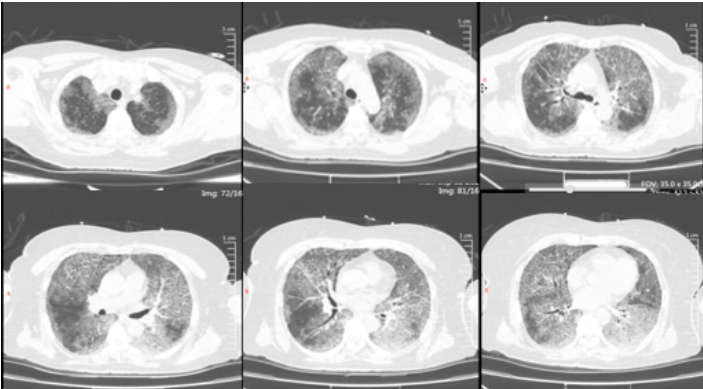

患者女性,53岁,因“间断气短半年,加重10天”入院。胸部CT提示双肺弥漫片状磨玻璃影,边缘模糊(图9)。支气管镜病理确诊肺泡蛋白沉积症,血气分析结果:pH 7.39,PaO2 31 mmHg,PaCO2 51 mmHg,BE -4.8 mmol/L。

图片

9  患者治疗前胸部CT

治疗方案:首次尝试全麻下大容量肺泡灌洗,术中注入37℃生理盐水500 ml后,患者指脉氧饱和度降至77%,遂停止治疗返回病房。次日采用VV-ECMO辅助支持,经右颈内静脉-右股静脉置管,正常全身抗凝,全身麻醉下行大容量肺泡灌洗术,灌洗期间停用全身抗凝,治疗后恢复全身抗凝。ECMO支持时间为24小时,患者未出现ECMO相关并发症;灌洗过程顺利。灌洗液从浑浊逐渐转为清亮(图10)